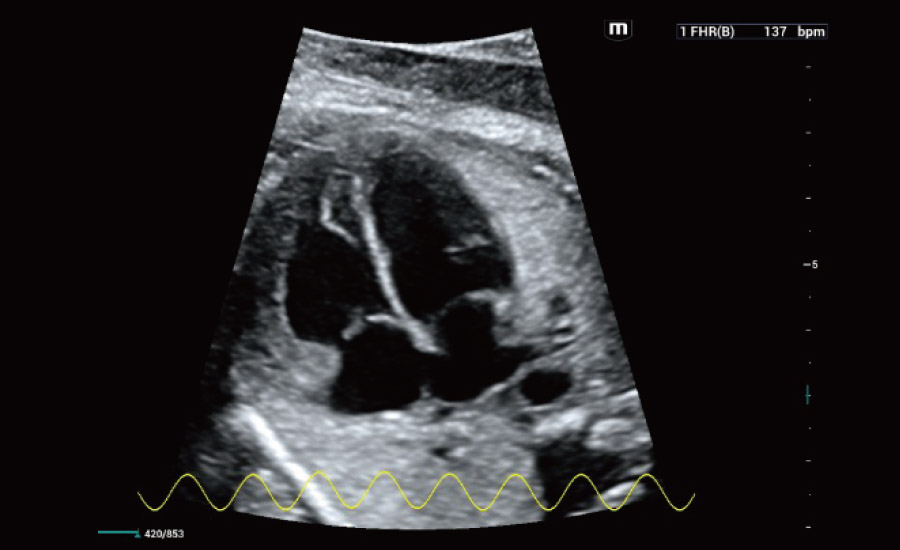

A tecnologia inovadora elimina as limita??es das tradicionais imagens com Doppler. Com resolu??o espacial e sensibilidade de fluxo ultra-altas, permite a detec??o de perfus?es de fluxos muito sutis e lentos, ampliando assim a aplica??o clĆnica da avalia??o qualitativa e quantitativa do ultrassom no cĆ©rebro fetal, rins, placentas, endomĆ©trios, ovĆ”rios etc.

Por meio da combina??o de algoritmos avan?ados e do conhecimento especĆfico da regi?o, a inovadora solu??o Smart Scene permite a identifica??o automĆ”tica das caracterĆsticas do tecido e fornece diagnĆ³stico especĆfico dos Ć³rg?os com informa??es completas. Com base na identifica??o automĆ”tica de cenĆ”rios, a solu??o realiza n?o apenas a varredura 2D inteligente com configura??es e medidas automĆ”ticas, mas tambĆ©m oferece informa??es 3D abrangentes em todas as etapas, desde a otimiza??o de imagens volumĆ©tricas atĆ© a difĆcil obten??o de planos 2D, e a quantifica??o durante todo o procedimento. Ele ajuda a reduzir em grande parte a dependĆŖncia de habilidades clĆnicas, ao mesmo tempo que aumenta a precis?o, a confian?a e a eficiĆŖncia no diagnĆ³stico.

ObstetrĆcia